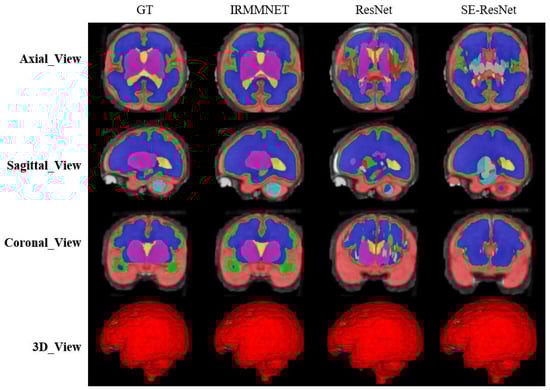

To validate the results of the proposed fused model (i.e., Multi-view-IRMMNET), we also applied the same fusion technique to the ResUNet and SE-ResUNet models, which yielded Multi-view-ResUNET and Multi-view-SE-ResUNET. The predicted 2D slices and 3D volumes of the proposed model, ResUnet, and SE-ResUNet are shown in Figure 10. Although ResUNet and SE-ResUNet successfully predicted outer classes, such as external cerebrospinal fluid (ECF), they failed to predict inner/deeper classes, like deep gray matter (DGM). It is conspicuous that the proposed model’s predictions for all classes were close to the given GT.

Table 7 presents the Dice, HD95, sensitivity, and specificity scores of the proposed Multi-view-IRMMNET, Multi-view-ResUNET, and Multi-view-SE-ResUNET models. The proposed Multi-view-IRMMNET model achieved the best segmentation results with a DSC of 0.791, HD95 of 21.66, sensitivity of 0.819, and Specificity of 0.980. The Multi-view-ResUNET model achieved less performance scores than those of Multi-view-IRMMNET. This model achieved a DSC of 0.758, and Multi-view-SE-ResUNET achieved a maximum DSC of 0.772. We can conclude that our proposed Multi-view-IRMMNET achieved the highest DSC score in comparison with the other models, namely, Multi-view-ResUNET and Multi-view-SE-ResUNET. Similarly, Multi-view-IRMMNET achieved the lowest HD95 score of 21.66, as compared to those of Multi-view-ResUNET and Multi-view-SE-ResUNET. Figure 11 shows the box plots of the DSC, HD95, sensitivity, and specificity scores of the proposed Multi-view-IRMMNET, Multi-view-ResUNET, and Multi-view-SE-ResUNET models. Multi-view-IRMMNET showed the highest Q3 quartile in the DSC and specificity plots. In contrast, Multi-view-IRMMNET’s median and maximum values remained higher in all plots compared to those of the Multi-view-ResUNET and Multi-view-SE-ResUNET models.

Figure 10. The segmentation results for the proposed Multi-view-IRMMNET, Multi-view-ResUNET, and Multi-view-SE-ResUNET models.

Entropy 24 01708 g010